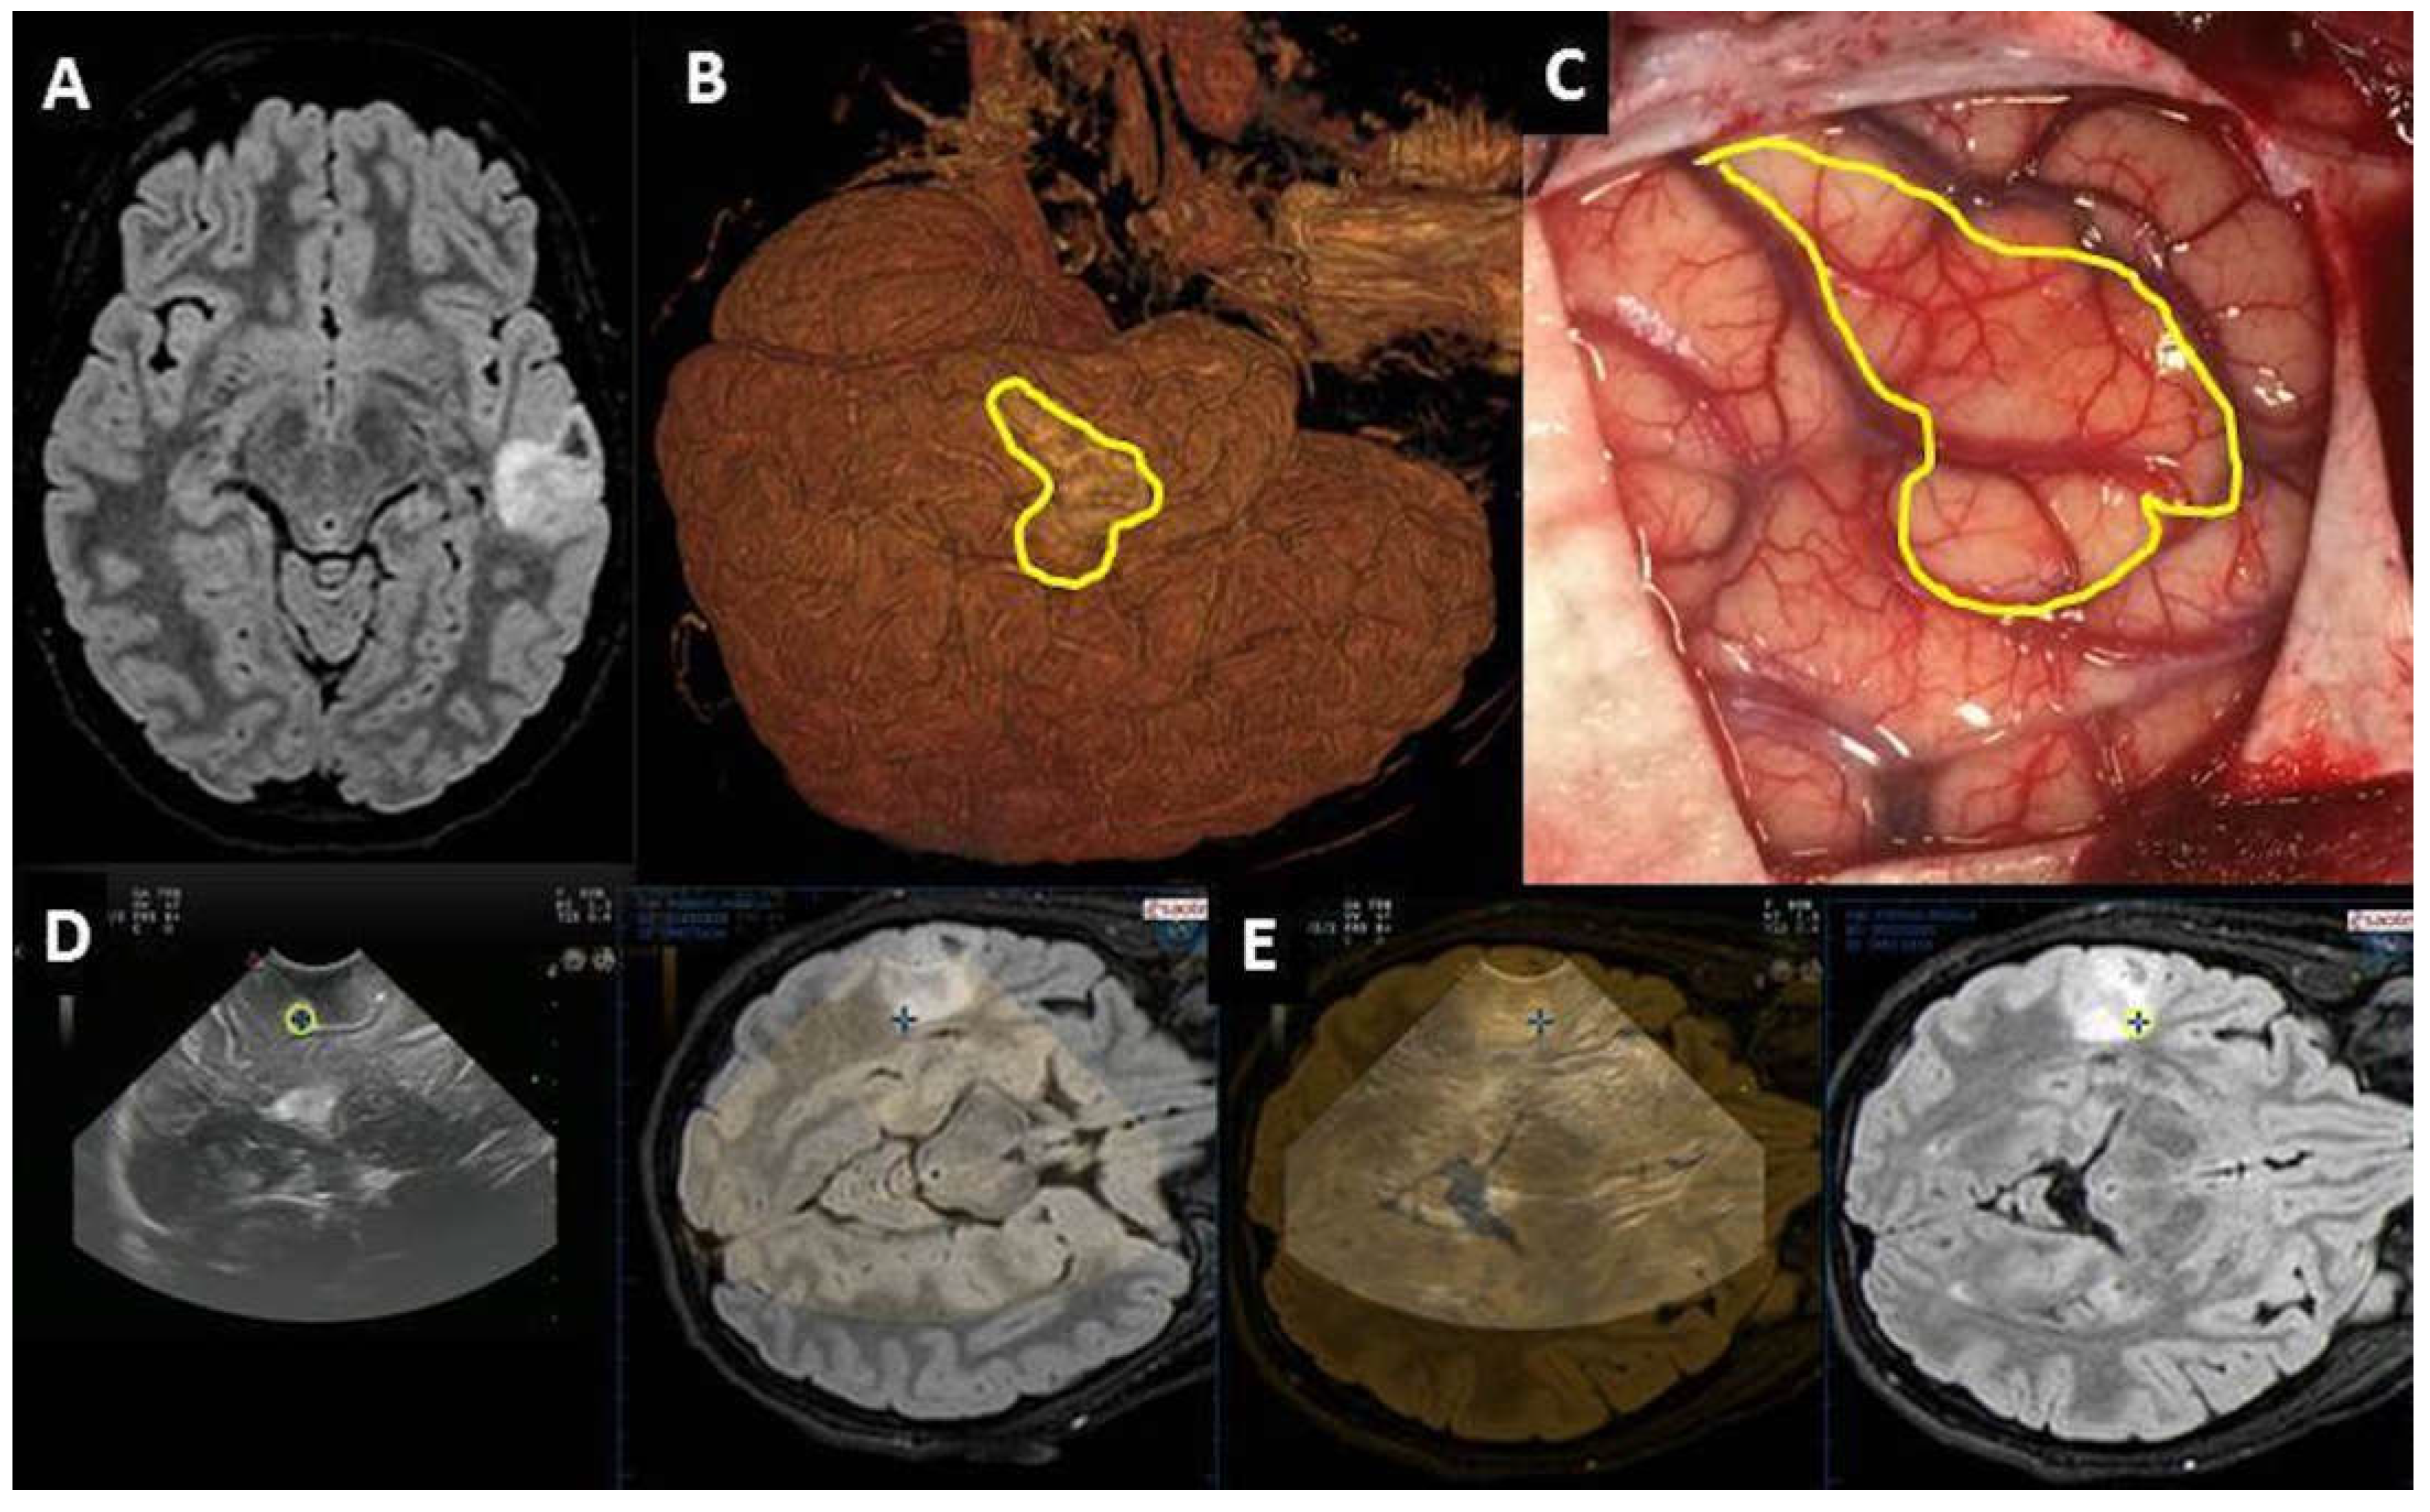

| Localization | Deep-seated lesion |

|

| Localization | Superficial lesion not distinguishable from brain parenchyma |

| Surgical route | Deep-seated lesion |